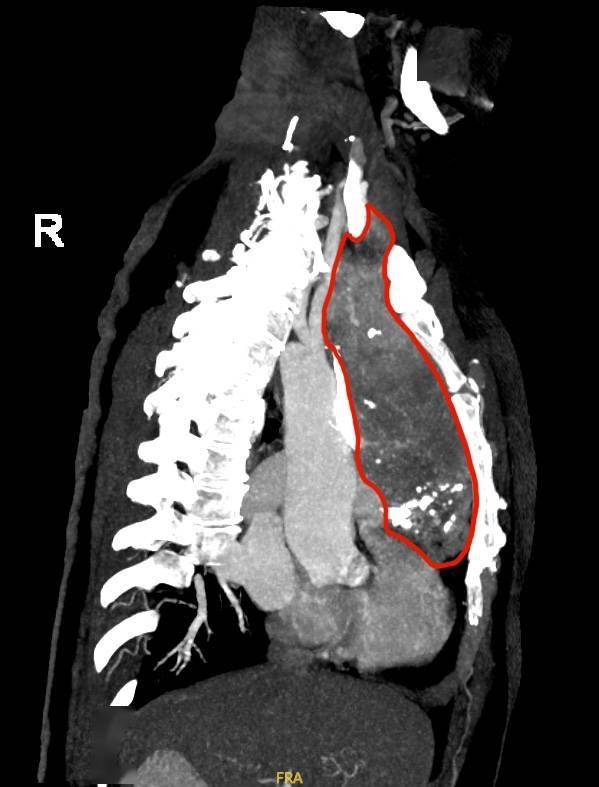

据林婆婆回忆 , 自己13年前曾做过一次子宫脱垂手术 , 术前检查已发现胸骨后甲状腺肿 , 但由于肿物不突出颈部 , 且没有特殊症状 , 一直没有太在意 , 也就没有治疗 。 但近几年来 , 林婆婆渐渐出现了面色潮红、不能平卧的状态 , 晚上只能半坐着睡觉 , 无法躺平 。 这背后的“罪魁祸首”正是不断增大的胸骨后甲状腺肿 。 近期复查CT检查显示 , 林婆婆的胸骨后甲状腺肿将心脏往下挤压 , 使得支气管变窄 , 就像一块顶心又顶肺的“大石头” 。

为了移开这块“心头大石” , 林婆婆辗转省内多家医院 , 最后来到了中山大学孙逸仙纪念医院耳鼻咽喉头颈专科 , 由咽喉头颈专科主任梁发雅副教授接诊 。 梁发雅副教授阅片后 , 发现胸骨后甲状腺肿已经长到了18厘米长、16厘米宽 , 且肿物的生长时间长 , 已经压迫气管和血液回流心脏的上腔静脉 , 形态为上窄下宽 , 难以单纯经颈部完成手术 。

CT显示甲状腺肿主体位于胸腔 , 与心脏及周围血管关系密切 , 上腔静脉受压迫

完善了相关检查 , 在耳鼻喉科主任黄晓明教授的主持下 , 梁发雅副教授联同胸外科陈炬教授、陈柏深副教授 , 麻醉科副主任林道炜教授、重症医学科主任何志捷教授与李伟超主治医师进行多学科联合会诊讨论 。 黄晓明教授指出 , 一般的胸骨后甲状腺大多可经颈部入路手术 , 松解甲状腺上级后将其“拔出”胸腔 , 但林婆婆的CT显示胸骨后甲状腺肿物为左侧甲状腺发展而来 , 不仅位置深 , 而且底部宽大 , 即使上级松解了也难以通过胸廓入口 。

“影像检查显示 , 肿物与纵隔内的主动脉、头臂动脉、上腔静脉、头臂静脉关系密切 , 上腔静脉已有压迫 , 为保证手术安全 , 经颈部联合胸骨劈开进行手术更为稳妥 。 此外 , 由于甲状旁腺、喉返神经等结构可能已经移位 , 手术中应用神经监测技术定位并保护双侧喉返神经 , 采用超高清内镜识别和精细被膜解剖法保留甲状旁腺功能 。 ”